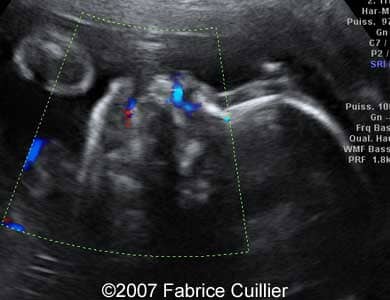

This is an example of bilateral cleft lip

Images 3, 4: Coronal (gray scale) and sagittal (color Doppler) images of the upper lip showing bilateral cleft defect of the upper lip.